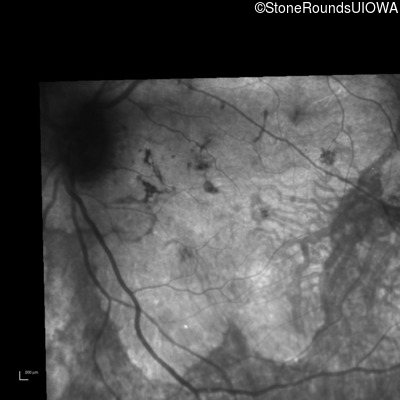

Infrared Fundus Photograph - Right - 20/25 -2

Exemplar